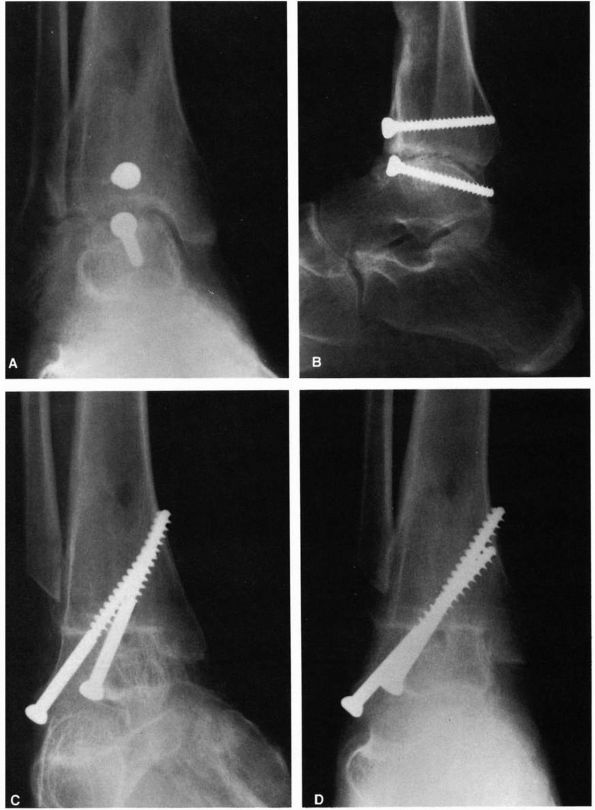

FIGURE 21-27. Ankle fusion. (A and B) Preoperative radiographs. (C and D)

Postoperative radiographs demonstrating a satisfactory ankle fusion using screw fixation. (Mann RA, Coughlin MJ. The Video Textbook of Foot and Ankle Surgery. St Louis: Medical Video Productions, 1991) |